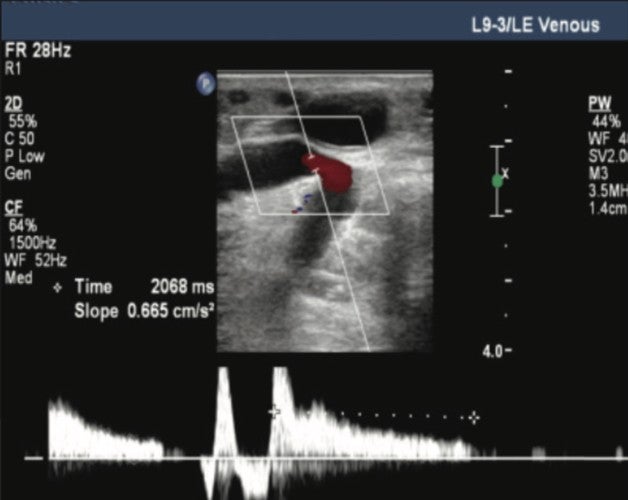

Figure 4. Reflux in perforator pre-Varithena treatment.

Pre-treatment: Color-flow Doppler ultrasound was performed on the left lower extremity and the varicose veins were mapped. Two access points were chosen in the left lower leg, mid-calf and distal calf.

Reflux was 3.2 seconds at the groin and 4.7 seconds at the proximal-mid thigh.